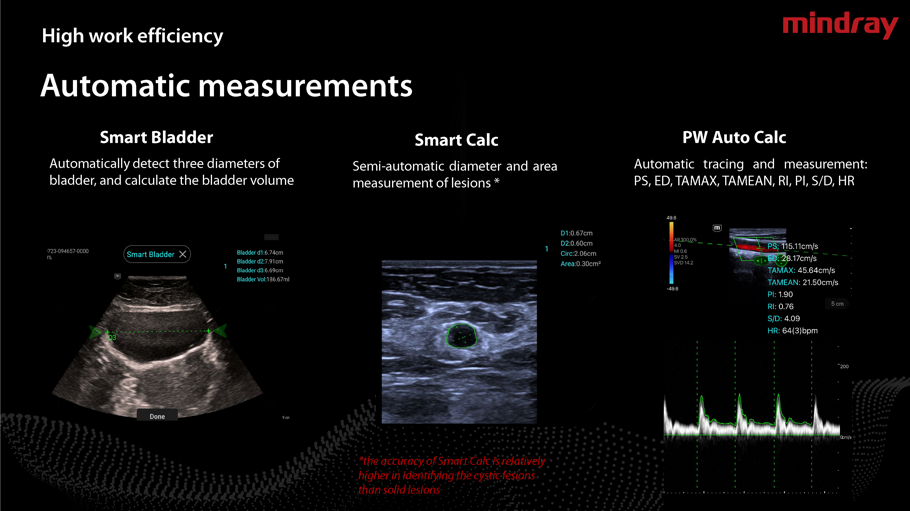

Caratteristiche Generali Sistemi Wireless Serie LU700 - , LK128:

- Alta risoluzione e tempo di utilizzo a lunga durata,fino a 4 ore di autonomia.

- Applicazione intuitiva,misure Doppler in tempo reale.

- Sonde a frequenza variabile,Color Doppler,Pulsed Wave,Power Doppler.

- Armonica di tessuto,Spacial Compound ,Connessione WiFi e USB ,velocità wireless elevato.

- Hiframe rate,Algoritmo propietario per l'eliminazione ritardi nell'immagine,Easy Report automatico con possibilità di invio tramite mail o altre applicazioni.

- Oltre 10 Preset di base e possibilità di personalizzarlo.